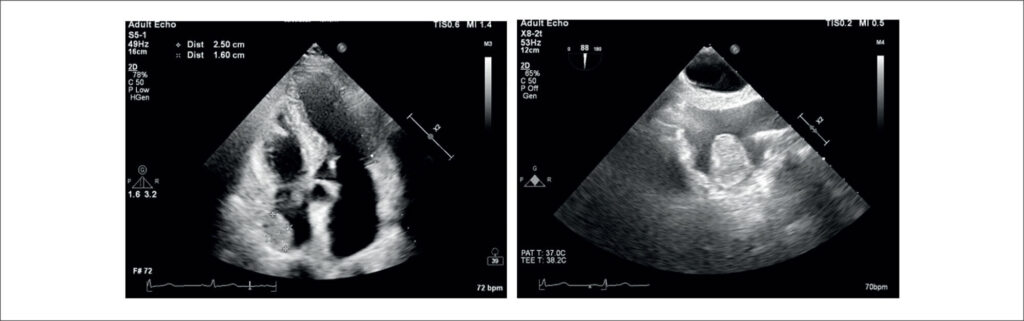

Cardiac Lipoma as an Incidental Finding in Cardiovascular Imaging Exam

The advent of cardiac imaging has ushered in an era where incidental findings can be detected using less invasive methods, even in asymptomatic patients. The clinical presentation of cardiac masses, characterized by their varying growth rates and diverse locations within the heart, poses a formidable challenge to cardiologists. Therefore, paramount importance lies in reducing the clinical burden and costs, considering the potential of cardiac imaging to optimize the clinical pathway. The most common cardiac masses in the right atrium include thrombi, vegetations, and neoplasia. Approximately 75% of primary tumors are benign, with myxomas comprising 50% of benign cases. Other benign tumors that usually may arise in the right atrium are rhabdomyomas, fibromas, fibroelastomas, and lipomas. Cardiac lipomas are rare, accounting for 2.9% to 8% of all benign cardiac tumors. They rank third in frequency after myxomas and papillary fibroelastomas. The literature suggests that 25% of cardiac lipomas are intramyocardial; 25% are extracavitary of epicardial origin, and 50% are intracavitary of subendocardial origin. Lipomas are well-encapsulated and homogeneous masses composed of mature fat. Although the etiology of cardiac lipomas is unknown, they can originate from any of the three cardiac tissues: subendocardial (the most common), pericardial, or myocardial.

The aim of this report is to present a case of an asymptomatic right atrial lipoma and to discuss the etiology, natural history, and optimal management strategies for right atrial lipomas.